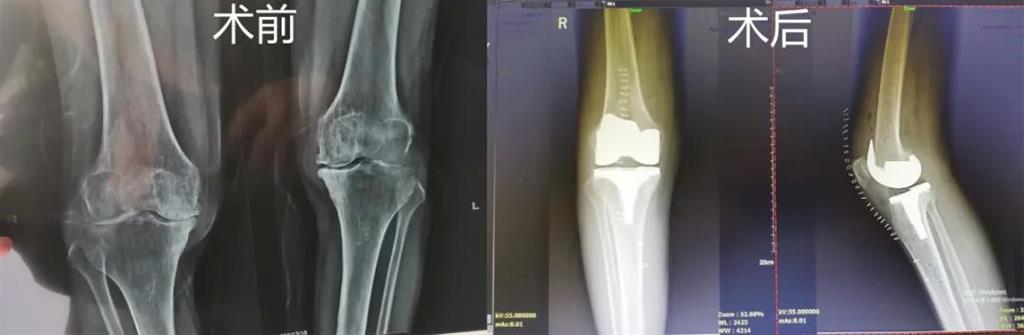

突破!和平國際醫(yī)院成功完成一例計(jì)算機(jī)導(dǎo)航膝關(guān)節(jié)置換術(shù)

最近,和平國際醫(yī)院骨科中心開展了一項(xiàng)新業(yè)務(wù)——計(jì)算機(jī)導(dǎo)航膝關(guān)節(jié)置換術(shù),而年邁78歲的李奶奶則幸運(yùn)地成為該手術(shù)的首個(gè)受益者。這也是溫州地區(qū)率先將骨科傳統(tǒng)手術(shù)與計(jì)算機(jī)導(dǎo)航系統(tǒng)相結(jié)合應(yīng)用的成功案例,也是和平國際醫(yī)院骨科中心在膝關(guān)節(jié)置換術(shù)方面所取得的一次重大突破!

李奶奶已經(jīng)被兩側(cè)膝關(guān)節(jié)疼痛困擾了5年左右時(shí)間,尤其是右側(cè)膝關(guān)節(jié),近一年來癥狀明顯加重,無法正常生活。經(jīng)過多方打聽,一家人來到和平國際醫(yī)院。

和平國際醫(yī)院副院長、骨科中心主任劉丹在診斷后發(fā)現(xiàn),老人雙側(cè)膝關(guān)節(jié)患有骨性關(guān)節(jié)炎,右側(cè)膝關(guān)節(jié)較為嚴(yán)重,而且關(guān)節(jié)磨損嚴(yán)重關(guān)節(jié)間隙基本消失。

經(jīng)過進(jìn)一步檢查后,劉丹帶領(lǐng)團(tuán)隊(duì)在計(jì)算機(jī)導(dǎo)航系統(tǒng)的輔助下,為老人實(shí)施了右側(cè)全膝關(guān)節(jié)置換手術(shù)。術(shù)中出血明顯減少,術(shù)后疼痛腫脹等反應(yīng)輕微,畸形矯正力線恢復(fù)理想,而且功能恢復(fù)快速,術(shù)后四天就可以下地行走。

據(jù)劉丹主任介紹,計(jì)算機(jī)導(dǎo)航膝關(guān)節(jié)置換術(shù)可以避免打開股骨髓腔,從而明顯減小手術(shù)創(chuàng)傷,減少術(shù)中出血,能夠更精準(zhǔn)地從三維角度調(diào)整手術(shù)截骨方向,恢復(fù)肢體對線,并能進(jìn)行精確的軟組織平衡,從而使患者獲得良好的術(shù)后功能恢復(fù)。